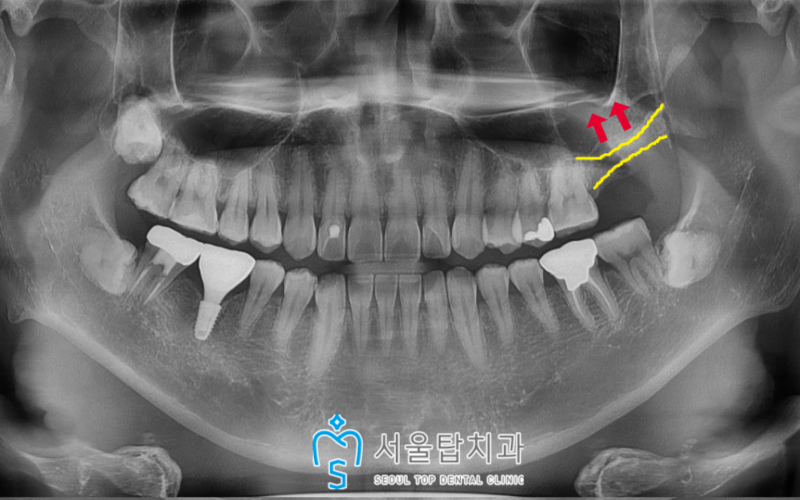

파노라마 사진을 촬영하여 확인해 보았더니

사랑니가 바로 앞

왼쪽 위 두 번째 큰 어금니(#27)의

치근(치아뿌리)을 일부 침범하게 되면서

치근 우식이 관찰되었습니다.